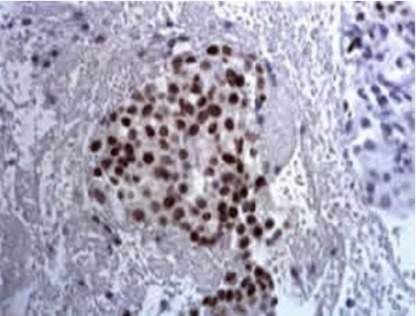

【產(chǎn)品介紹】本試劑盒有助于急性白血病的鑒別診斷。急性粒細胞白血病常以強陽(yáng)性為主;急性單核細胞性白血病多為弱陽(yáng)性;急性淋巴細胞白血病和巨核細胞白血病時(shí)則為陰性。具有簡(jiǎn)便易操作,染色效果好等優(yōu)點(diǎn)。

本試劑盒有助于急性白血病的鑒別診斷。急性粒細胞白血病常以強陽(yáng)性為主;急性單核細胞性白血病多為弱陽(yáng)性;急性淋巴細胞白血病和巨核細胞白血病時(shí)則為陰性。具有簡(jiǎn)便易操作,染色效果好等優(yōu)點(diǎn)。